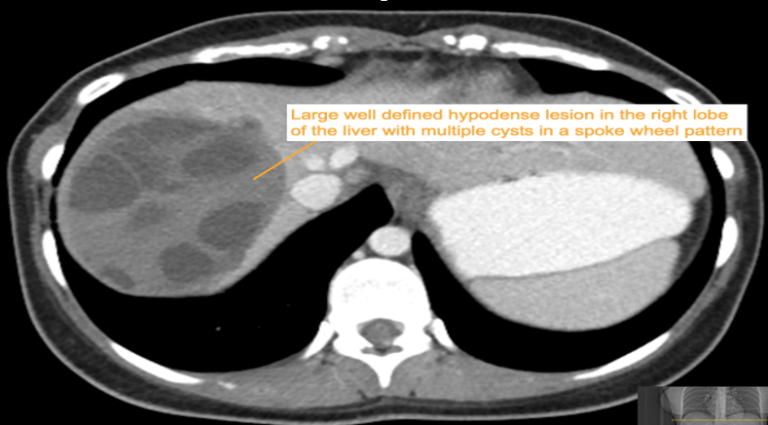

CASE 3 – A 23-year-old woman presents with 3 weeks of right upper quadrant (RUQ) pain associated with early satiety. The patient has no significant past medical history. She was born in Iraq and migrated to Australia from Syria 2 years prior to presentation. Preliminary blood results demonstrate moderate liver function test (LFT) derangement.

EXPLANATION -The case demonstrates classical appearance of a hepatic hydatid cyst. There is a well-defined rounded lesion in right lobe of liver with multiple small daughter cysts within. The fluid in the cysts can be of variable density depending on the proteinaceous contents (more protein = more dense). The thick internal septae can give a “spoke wheel” appearance as in this case. Curvilinear calcifications represents the inactive stage of the disease.

Hydatid diseases a parasitic zoonosis, caused by the larval stages of the Echinococcus granulosus .

- E. granulosusis found worldwide, however the highest rates of infection are seen in the Mediterranean and Middle Eastern regions, North Africa and South America.

- Hydatid cyst can occur anywhere in the body, the most commonly affected organ is the liver (76% of cases), followed by lung (15%) and spleen (5%).

- Classically there is a large ‘parent cyst’ which contains numerus peripheral ‘daughter cysts’.